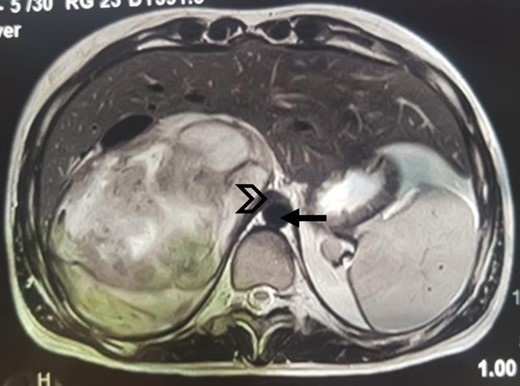

An MRI angiogram to assess the vascular relationships of the tumor revealed a 125 × 110 × 95 mm3 well-bounded, oval, slightly heterogeneous right adrenal mass with a mixed T2 signal and hypointense T1 signal. Angiographic sequences showed no portal venous thrombosis; the lesion was adherent to the right liver and the inferior vena cava (IVC), which was compressed but remained permeable, and came into contact with the superior mesenteric artery and the superior mesenteric vein, which were also permeable. The hepatic pedicle was also slightly pushed forward (Figs. 2 and 3).

MRI, well-limited oval right adrenal mass, slightly heterogeneous mixed T2 signal (arrow: aorta; arrowhead: compressed IVC).